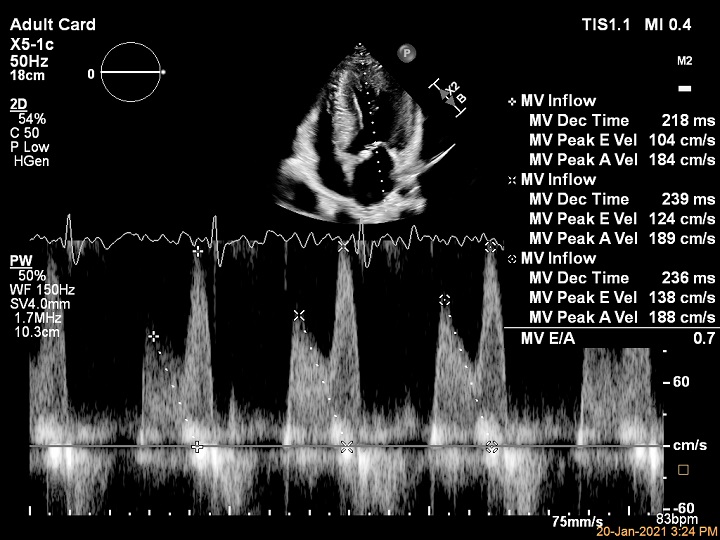

AI がルーチンの心機能計測をアシスト Auto Measure は AI が自動で 2D またはドプラの計測を行う機能です。検者の熟練度によるばらつきや、さまざまな状況下においても一貫した計測結果が得られるよう日々の計測をサポートします。Transcend に搭載された Smart Doppler View ID 機能は、ドプラ計測の際に AI が現在スキャンしている断面を認識し、計測の際に必要な計測項目をタッチスクリーンに表示します。検者が計測項目を探す手間を省略でき、検査の効率化をもたらします。